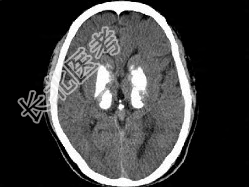

- 单项选择题男,49岁, 反复发作性癫痫,双手震颤5年, 伴头昏行走不稳,生化检查: 血清钙降低,血清磷升高, 请根据所提供图像,选择最可能的诊断 ( )

A、Fahr病

B、一氧化碳中毒性脑病

C、霉变甘蔗中毒

D、肝豆状核变性

E、甲旁低